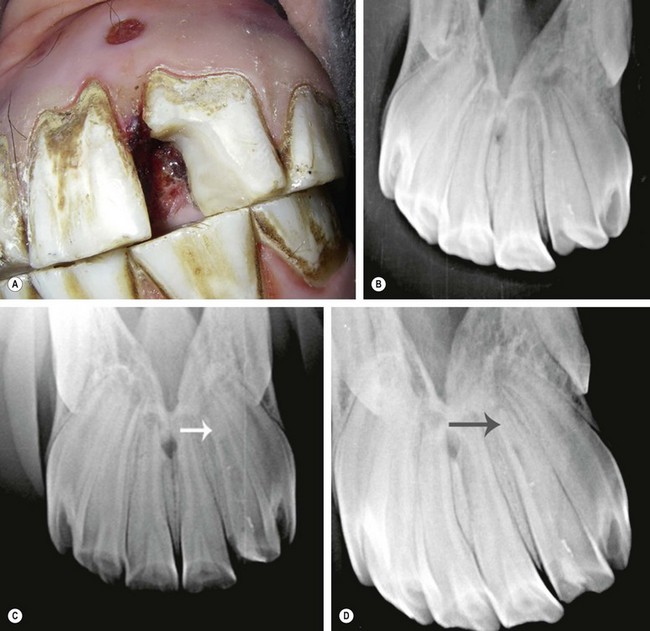

Fig. 21.13 Application of Type II glass ionomer (GI) cement restoration. GI restorations should only be applied after careful and cautious planning because of the hypsodontic eruption of equine teeth. (A) Tooth resorption on the vestibular aspect of the 3rd incisor of a senior horse. (B & C) Cavity preparation of the lesion involved osteoplasty and extensive subgingival debridement of all three dental tissues

(Modified Honma Stage 3 lesion).

image

(D & E) A glass ionomer restoration was selected due to the uncertain etiology of the lesion and based on extrapolated applications in human and small animal patients. (F) 1-year follow-up demonstrates retention of the restorative with surface pitting and possible marginal leakage.